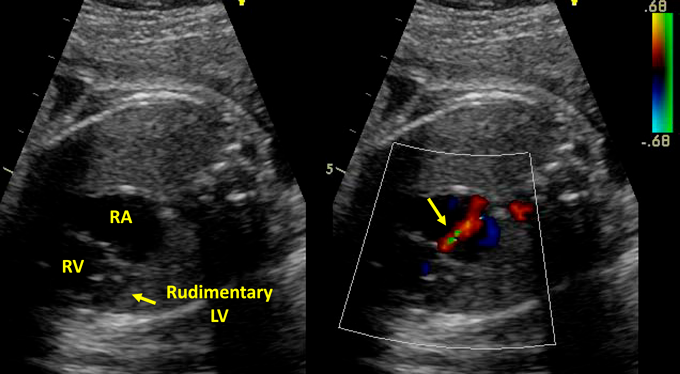

Fig. 5 Countercurrent angiography shows sinus of Valsalva aneurysm of noncoronary cusp with continuous flow to RA (arrow)

See Movie C. LV, left ventricle; RA, right atrium; RCCA, right common carotid artery; RSCA, right subclavian artery; RV, right ventricle

出生後の心エコー所見からバルサルバ洞動脈瘤破裂が疑われ,胎児期に三尖弁逆流と判断していた血流は,この短絡血流であると考えられた.診断確定のためのさらなる精査として,心臓カテーテル検査は児への侵襲度が高いこと,造影CT検査や心臓MRI検査は体格が小さく詳細な評価が困難であることから,児への侵襲が比較的少ない末梢逆行性大動脈造影を施行した.末梢逆行性大動脈造影は右橈骨動脈から行い,大動脈弁無冠尖のバルサルバ洞が下方へ突出し,そこから右房内に流入する血流を認め,バルサルバ洞動脈瘤破裂と診断した(Fig. 5, Movie C).診断確定後,手術侵襲や予後も含めて家族に説明したところ,積極的な治療を希望しなかった.そのため,外科手術は行わず緩和的医療を行う方針とした.出生後より開始していたアルプロスタジルの投与は継続としたが,狭小な卵円孔に対してのバルーン心房中隔裂開術は施行しなかった.むしろ,狭小な卵円孔により急激な肺血流の増加が抑えられ,比較的安定した状態を維持することが可能であった.しかし,徐々に心不全と低酸素血症が進行し,日齢64に永眠した.ご家族の希望がなく,病理解剖は施行しなかった.